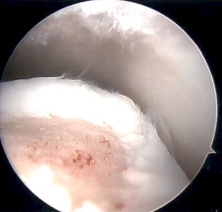

Arthroscopy Approaches

Anterolateral / anteromedial

- anterior 50 - 60% lesions

Anterolateral osteochondral lesion accessible via plantarflexing the ankle

Excision + microfracture / cartilage restoration